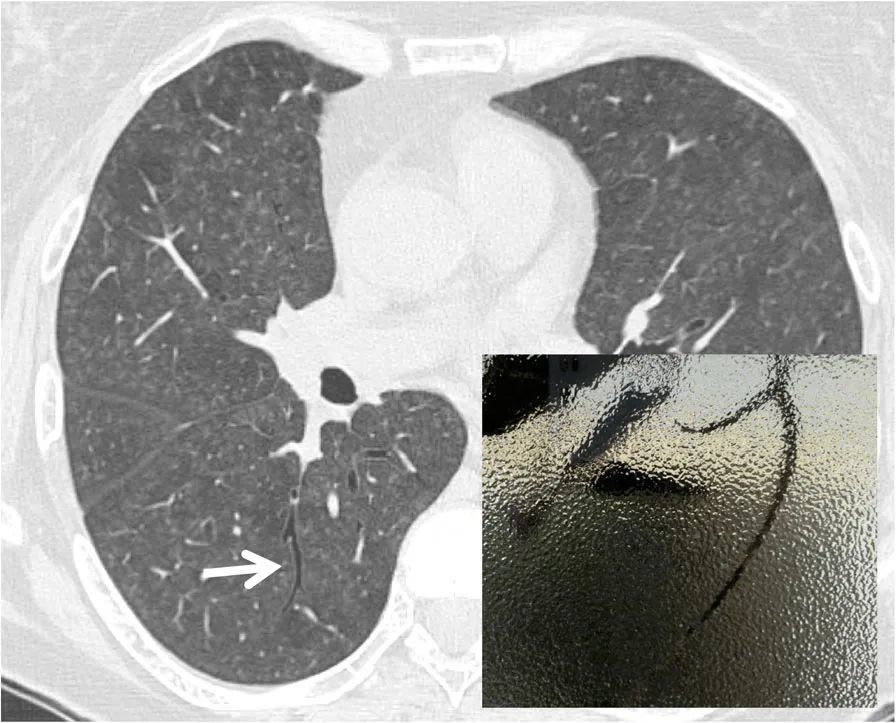

【病例讨论】弥漫性实质性肺疾病1例求解 [病例帖]